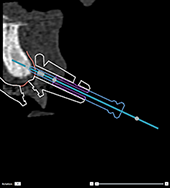

Incorrect: the anchor pin sleeve

protrudes through the radiographic guide and the template will

not fit into the patient’s mouth. |